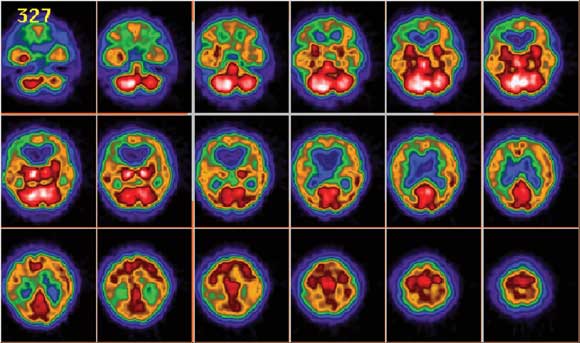

Magnetic resonance imaging (MRI) scans of the brain showed ventricular enlargement, supratentorial white-matter hyperintensities, and extensive leptomeningeal enhancement in the posterior fossa, brain stem and basal cisterns, with extension along the cranial nerves (Figure 1). The MRI results were reported as consistent with neurosarcoidosis. A SPECT (single-photon emission computed tomography) scan, undertaken to differentiate possible causes of dementia, demonstrated global hypoperfusion (Figure 2).